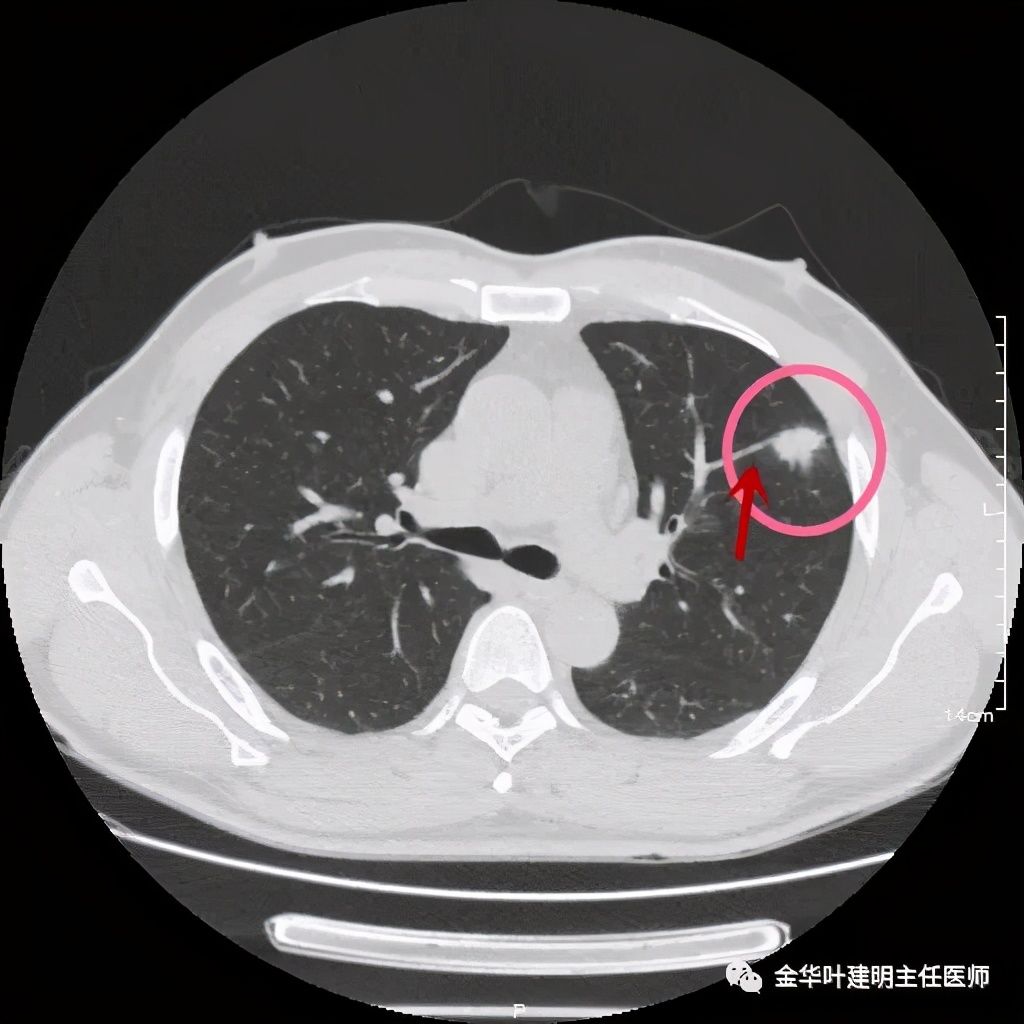

病灶实性,但收缩力弱,绿色箭头示病灶边缘有一圈晕征(模糊且均匀)

病灶实性,但收缩力弱,没有细毛刺征,实性部分比较圆润,绿色箭头示病灶边缘有一圈晕征(模糊且均匀)

此层面红色箭头示有卫星灶,粉色箭头示主病灶

红色示卫星灶,粉色示病灶,绿色示边缘晕征

此层面相对最不舒服,病灶表面不平整。桔色箭头示血管进入病灶,但仍有绿色箭头示病灶有晕征(边缘是模糊的,不似肿瘤那种细毛刺且相对清楚轮廓)